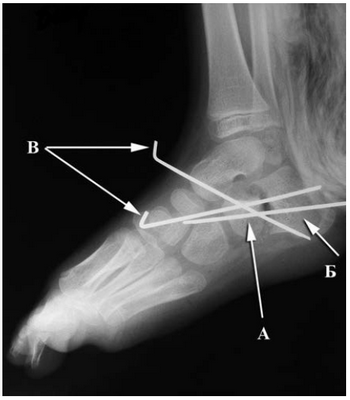

Рис. 1. Направление выполнения остеотомии пяточной кости из доступа по внутренней поверхности стопы

По наружной поверхности стопы разрез выполняли от заднего края наружной лодыжки до дистального конца заплюсневой пазухи. После разреза кожи, подкожной жировой клетчатки и тыльной фасции стопы мобилизовали сухожилия малоберцовых мышц. Далее производили артротомию подтаранного сустава и пересекали таранно-пяточную связку. Затем тупо выделяли и пересекали подошвенную связку. После этого после рассечения надкостницы выполняли остеотомию пяточной кости в направлении, встречном по отношению к остеотомии, произведенной из внутреннего доступа (рис. 2). Фрагмент пяточной кости (который включает sustentaculum tali), полученный в результате остеотомии, транспонировали кнутри, кверху и ротировали наружу. Целью производимых смещений являлось создание надежной опоры под головку и шейку таранной кости в виде sustentaculum tali, что нормализовало соотношение костей в подтаранном и таранно-пяточно-ладьевидном суставах. Фрагменты пяточной кости после их смещения на необходимую величину фиксировали спицами Киршнера (рис. 3). Перед ушиванием раны по внутренней поверхности стопы внутренний отдел капсулы таранно-пяточно-ладьевидного сустава укрепляли с помощью ее дупликатуры, которую формировали швами с использованием толстых лавсановых ниток.

Рис. 2. Направление выполнения остеотомии пяточной кости из доступа по наружной поверхности стопы

Рис. 3. Интраоперационная рентгенограмма стопы после выполнения корригирующей остеотомии пяточной кости: А — передний фрагмент пяточной кости; Б — задний фрагмент пяточной кости; В — фиксирующие спицы